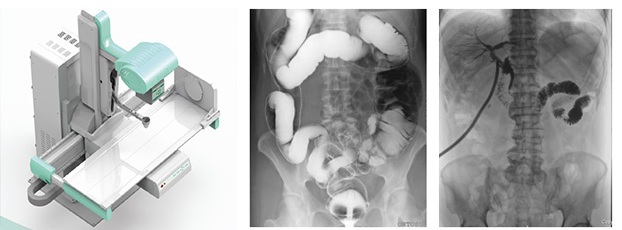

動態DR是一款多功能DR,能夠數字拍片、數字透視、數字造影。

動態DR具有大幅面(17inch×17inch)高清拍片、大幅面(17inch×17inch)透視、視頻實時保存回放、可視化造影、毫秒級點片等基礎功能,以及斷層融合、數字減影等延展性功能。

普愛醫療作為全球較好的數字影像設備供應商,專注于DR系列產品的技術創新,在全國范圍內率先推出動態DR。以其“一機多用”集常規拍片、胃腸、透視、造影于一體的多功能作用深受放射科臨床醫生的鐘意。